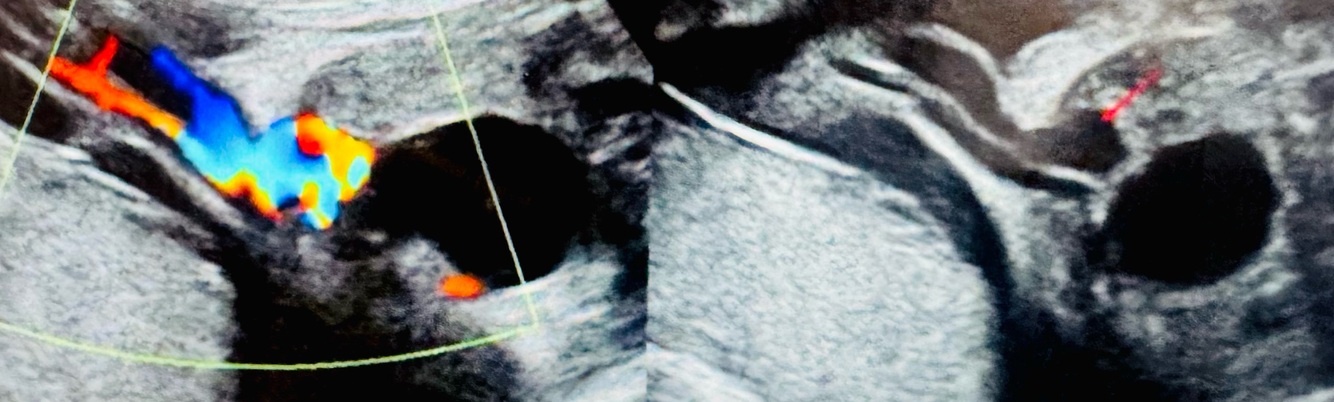

Q

What pathology? Describe. What can it be confused with and how can you tell the difference? When does it occur?

A

Umbilical vein varix

A locally dilated segment of the umbilical vein

Can be confused with umbilical vein cyst. (Varix has color flow cysts dont)

Can occur when there is volume overload

ASSOCIATED WITH TRISOMY 21